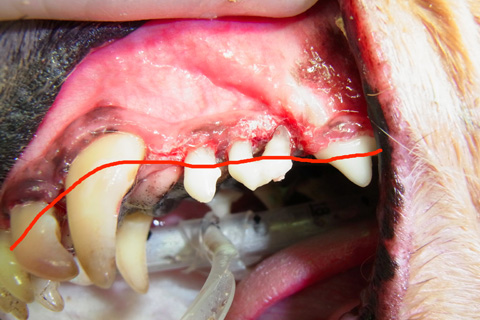

ハグキが溶けてしまっています。本来赤い線のところまでハグキです。

歯のレントゲン写真